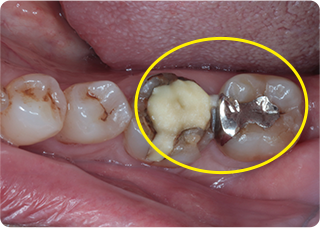

精密根管治療③

術前

術後

| 主訴 | 奥歯で噛むと痛い |

| 治療期間/回数 | 1ヵ月、4回 |

| 価格(税込) | 88,000円(税込) |

| リスク・副作用 | 病変再発、歯根破折の可能性 |

| ポイント | う蝕検知液を用い、むし歯の取り残しが無いようにし、ラバーダム防湿を行い、無菌的に根管治療を行った。根管充填材は、殺菌作用の強い保険適応外のMTAセメントを使用した。 |